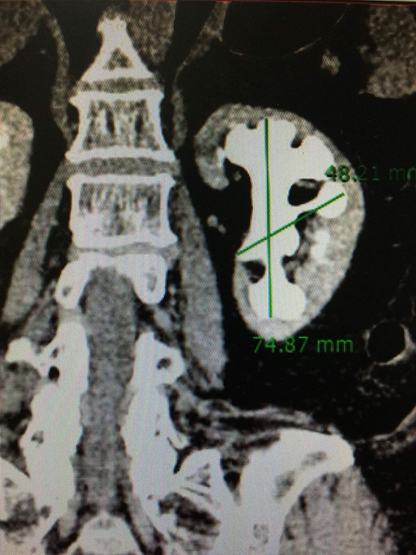

Sỏi san hô kích thước 74mm x 48mm chiếm hết toàn bộ thận và các đài thận

Khoa Tiết niệu Bệnh viện Đại học Y dược TP.HCM vừa tiếp nhận bà Võ Thị S., (59 tuổi, ngụ tại TP.HCM), nhập viện vì đau hông trái kéo dài nhiều năm. Sau khi thăm khám và chụp CT – Scan, các bác sĩ Khoa Tiết niệu phát hiện người bệnh bị sỏi san hô kích thước 74mm x 48mm, chiếm hết toàn bộ thận và các đài thận. Theo ThS.BS Nguyễn Hoàng Đức – Trưởng khoa Tiết niệu, đây là trường hợp sỏi thận phức tạp, hiếm gặp. Nếu không điều trị, sỏi sẽ tàn phá làm mất chức năng thận. Mặt khác, sỏi còn có thể gây ra những đợt nhiễm trùng thận, nguy hiểm tính mạng.